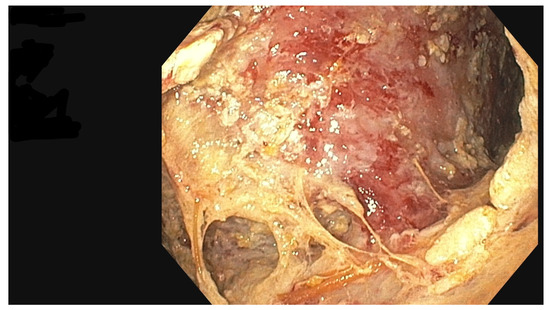

The PEN procedure was performed under general anesthesia with endotracheal intubation in the supine position. Percutaneous endoscopic necrosectomy was performed under the guidance of ultrasound (using a Logiq P9, convex C1-6 MHz probe) and fluoroscopy. Following the establishment of percutaneous drainage, Cook Medical Acrobat 2 AWG2-35-45 guidewire was inserted and looped inside the lumen of the necrotic collection (Figure 1 and Figure 2) to be followed by implantation of a fully coated self-expandable Evolution® esophageal controlled-release stent 120 mm or 150 mm in length and 20 mm in diameter (Figure 3 and Figure 4). A flexible Evis Exera III CF-H190L endoscope–gastroscope (Olympus) was then inserted into the necrotic collection through the lumen of the esophageal stent, and a percutaneous endoscopic necrosectomy procedure involving mechanical removal of necrotic tissue from the collection under direct endoscopic image guidance was performed (Figure 5, Figure 6 and Figure 7). A Dormia basket (Figure 8) was used to remove necrotic tissue. In the course of the percutaneous endoscopic necrosectomy procedure, the necrotic collection was extensively flushed with physiological saline, and the contents from the reservoir were aspirated. The PEN procedure was considered complete upon removal of demarcated necrotic tissues or upon bleeding from the inflammatory granulation tissue within the necrotic collection. If subsequent percutaneous endoscopic necrosectomy procedures were required in the same patient, the esophageal stent was left in the percutaneous position, and one or two 16 Fr silicone drains (depending on the size of the collection) were inserted into the lumen of the necrotic collection through the stent to maintain patency. The drain(s) were used to flush the collection with 100 mL of physiological saline 6 times a day. Following the completion of endoscopic treatment using percutaneous access, the esophageal stent was removed, and the stenting site was secured with a stoma bag to drain the remaining contents from the residual necrotic collection (Figure 9).

Figure 7. Percutaneous endoscopic necrosectomy using a Dormia basket. Source: Department of General, Gastroenterological, and Oncological Surgery, L. Rydygier Regional Hospital in Toruń.

Figure 8. Percutaneous endoscopic necrosectomy procedure, endoscopic view. Source: Department of General, Gastroenterological, and Oncological Surgery, L. Rydygier Regional Hospital in Toruń.